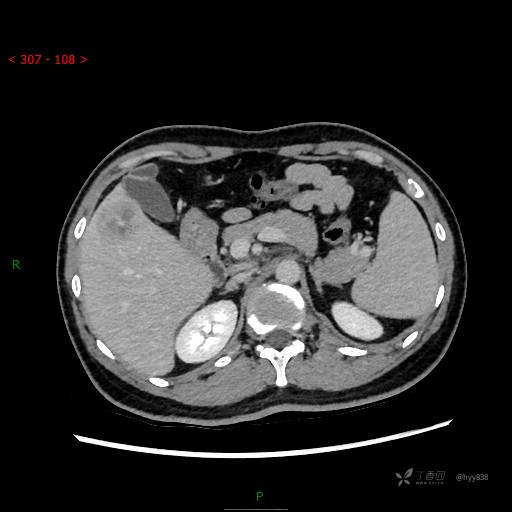

年轻男性,肝脏孤立结节、邻近包膜如此内陷,不知“坑”为何物---(结果公布)

简要病史: 患者1月余出现腰背部疼痛,以夜间疼痛为甚,伴双下肢胀痛,无腹胀、腹痛,无咳嗽、咳痰,无头晕、头痛等症状,门诊超声提示肝结节状占位

临床诊断:肝占位

增强动脉期